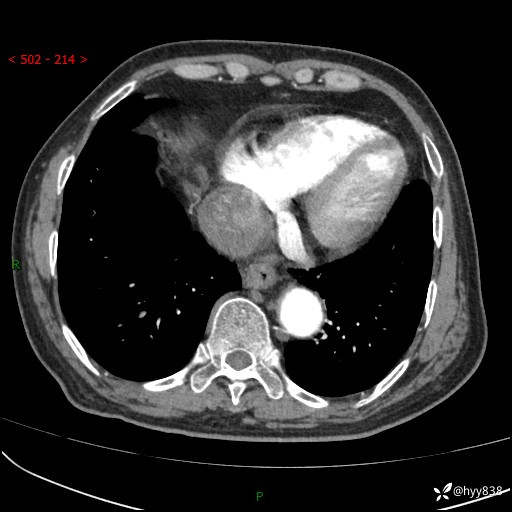

老年男性,检查发现心脏肿物1周余。少见病例,请讨论---结果公布~

主诉:检查发现心脏肿物1周余。

现病史:患者一周余前因腹胀就诊我院消化科门诊,查心脏彩超提示右房内异常回声(粘液瘤?),无明显心慌、气喘、胸闷,无明显胸痛、咳嗽咳痰等不适,活动量增加后出现心慌、气喘不适。现为求进一步治疗,就诊我科,门诊遂以“心脏肿物”收入院。 自发病以来,精神睡眠一般,食欲尚可,大小便正常,体力下降,体重无明显变化。

胸部CT平扫+增强